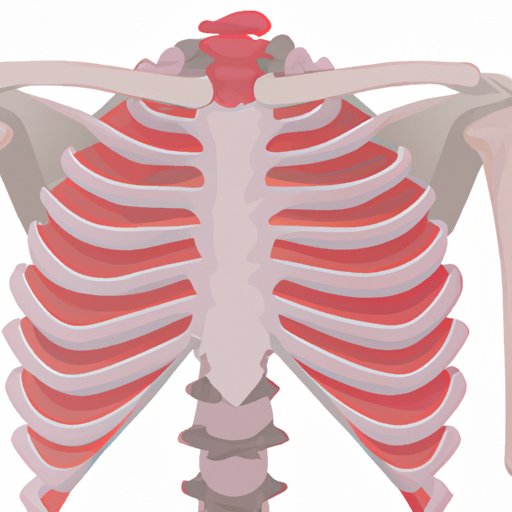

Sore Ribs: When It’s More than Just a Muscle Strain

Understand the anatomy and function of the ribcage, explore common causes of sore ribs, discuss the symptoms and treatment options, and offer strategies for prevention and management.

Why Does My Ribcage Hurt When I Cough? Understanding the Causes and Seeking Treatment

Discover the root causes behind ribcage pain during coughing, and learn how to recognize serious warning signs. With practical tips and insights into the relationship between the respiratory system and the ribcage, you can take action to alleviate discomfort, promote healing, and get the care you need.